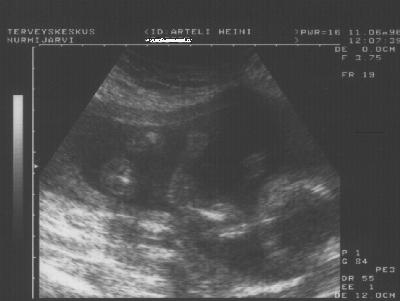

Penvis n.3kk ikäisenä.

Hannu Matilda 5kk ennen syntymäänsä.